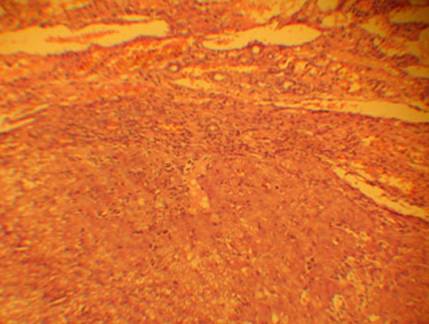

Мульти-монолобулярный постнекротический активный цирроз печени.